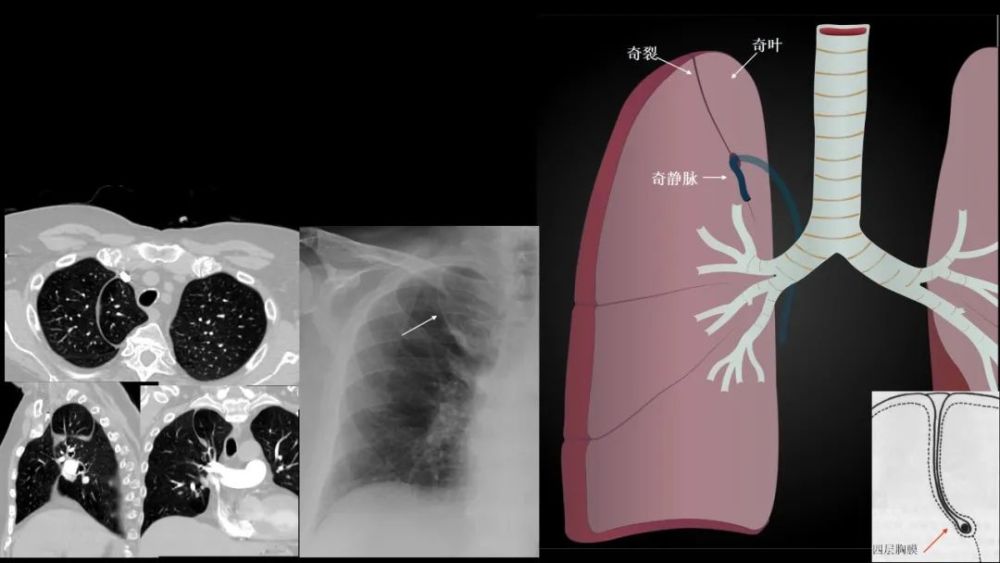

奇 裂

奇静脉分隔右肺上叶尖段

不是真正的附叶 , 因为没有自己的支气管 解剖标本的发生率为1% , M:F=2:1

X:细线状隆起(相对于纵膈) , 穿过右肺尖 , 前位上纵膈胸片可?气体

CT: 奇裂从SVC和气管后穿过